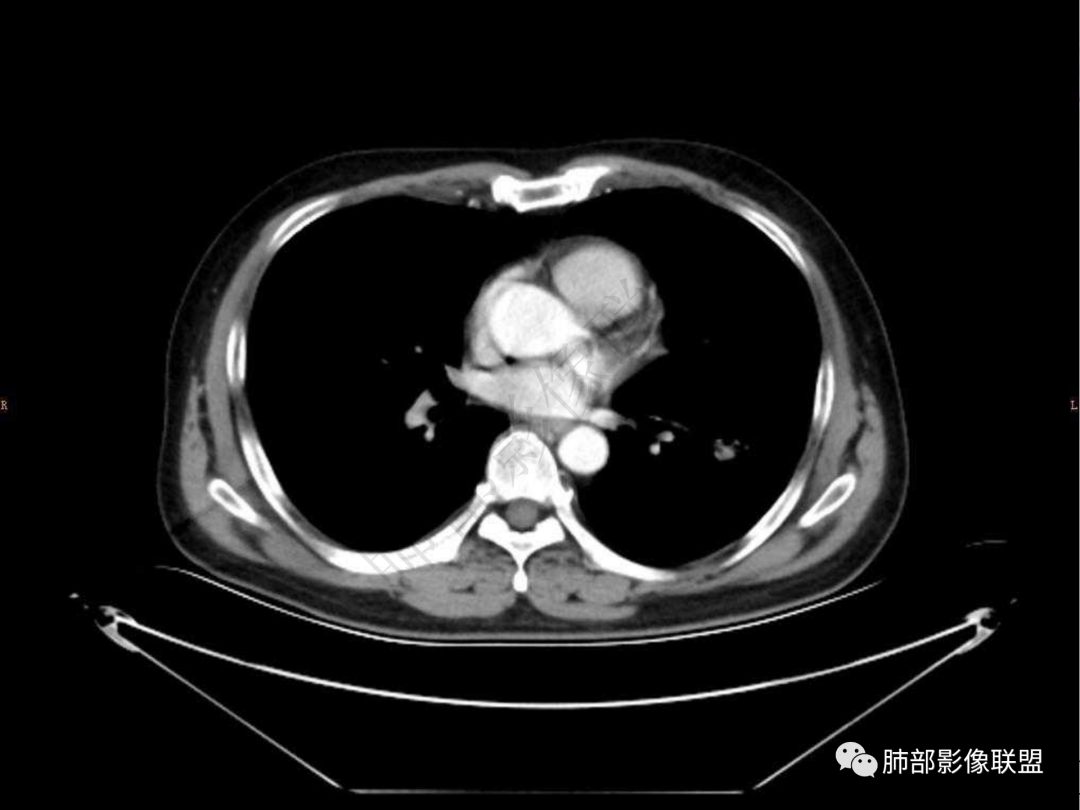

2.左肺下叶团片影,跨背段及内前基底段,实性部分类椭圆形,密度不甚均匀,可见毛刺及棘状突起,未见典型分叶及胸膜凹陷。病灶上下缘可见相应肺段支气管旁进侧出,管壁轻度增厚,未见狭窄阻塞。

4.实性部分不均匀环形强化并显示一小范围低密度坏死区或空洞。较之肺窗,整体纵隔窗范围较小,提示病灶并不十分密实。抑或为不同时段图像。

肺脓肿:可宽基底与胸膜相连,附近胸膜增厚——炎性特点

肺脓肿:环形强化,强化较显著。如出现明显囊壁样强化甚至边缘“憩室”样突出,高度支持肺脓肿。